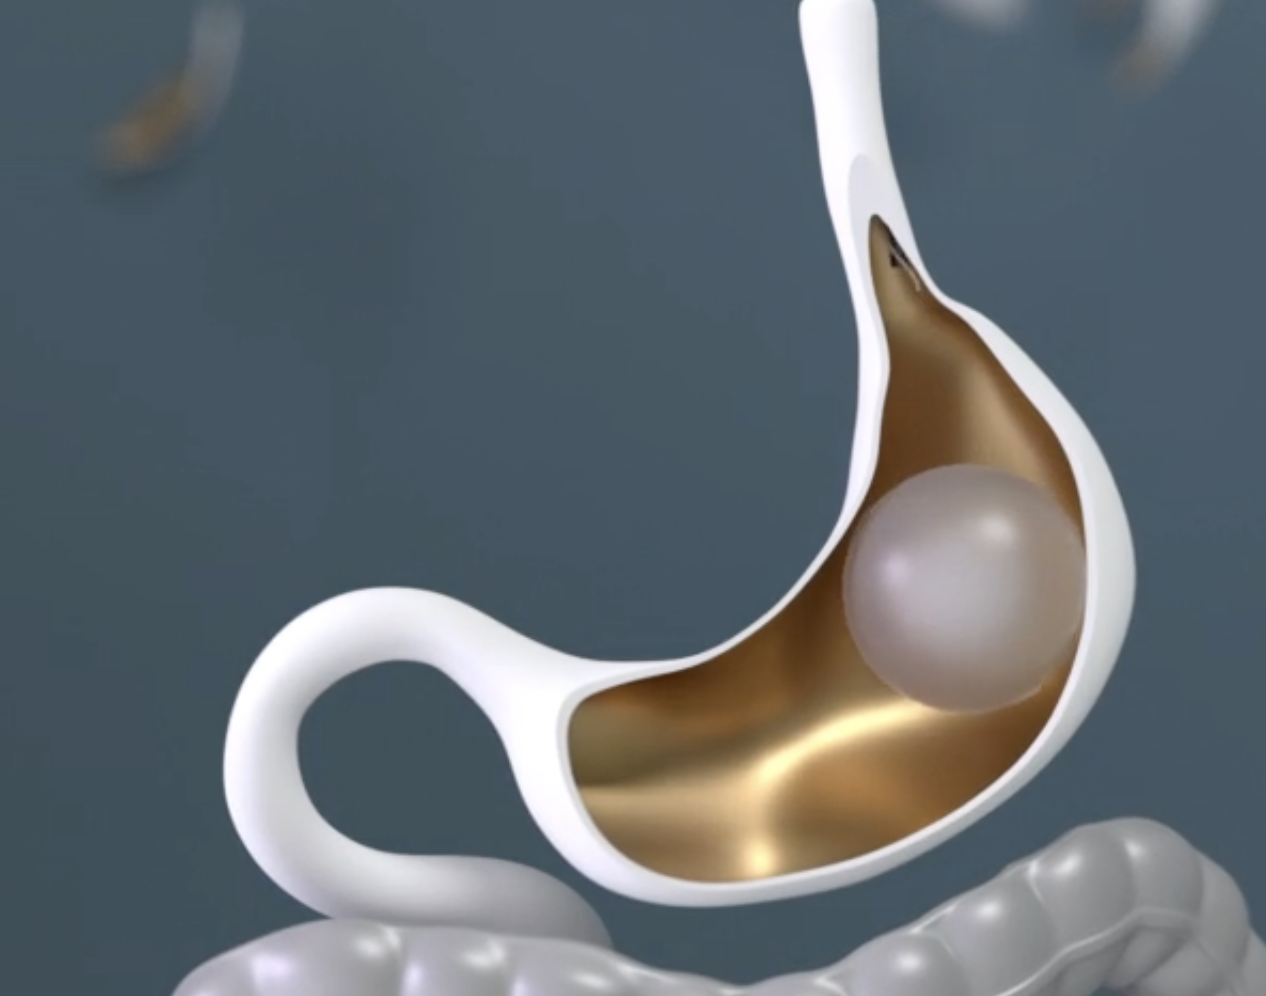

View Article 5 Gastric Balloon Types Explained: Which One is Best?

View Article 5 Gastric Balloon Types Explained: Which One is Best? Everself Team

View Article Gastric Balloon Before and After: What to Expect

View Article Gastric Balloon Before and After: What to Expect Everself Team

View Article 6-Month Gastric Balloon Results: What to Expect

View Article 6-Month Gastric Balloon Results: What to Expect Everself Team

View Article Common Misconceptions About Non-Surgical Gastric Balloon

View Article Common Misconceptions About Non-Surgical Gastric Balloon Everself Team

View Article How Effective Is The Gastric Balloon Procedure?

View Article How Effective Is The Gastric Balloon Procedure? Everself Team